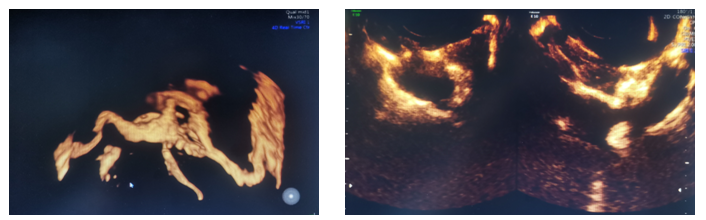

患者为31岁不孕症女性,在西咸院区产科就诊后,临床医生接诊后认为需要超声检查以评估宫腔情况及双侧输卵管通畅性。超声诊断中心任媛主治医生全程配合,为患者行四维超声宫腔成像及输卵管超声造影检查,整个过程顺利,耗时短,患者无不适,该项检查为临床及患者提供了客观影像学信息。

输卵管超声造影检查是通过向宫腔内注射超声造影剂,使宫腔及输卵管显影,可清楚观察到宫腔、宫角、双侧输卵管的形态及与卵巢的位置关系,21点技巧中心